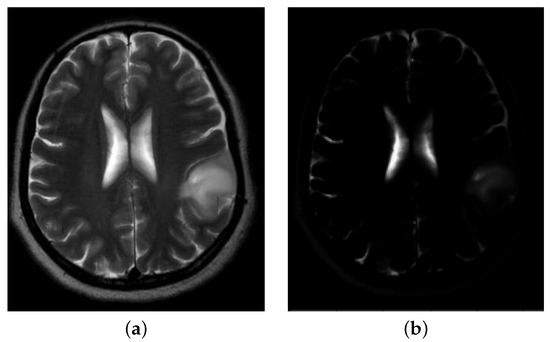

3.2. Post-Processing